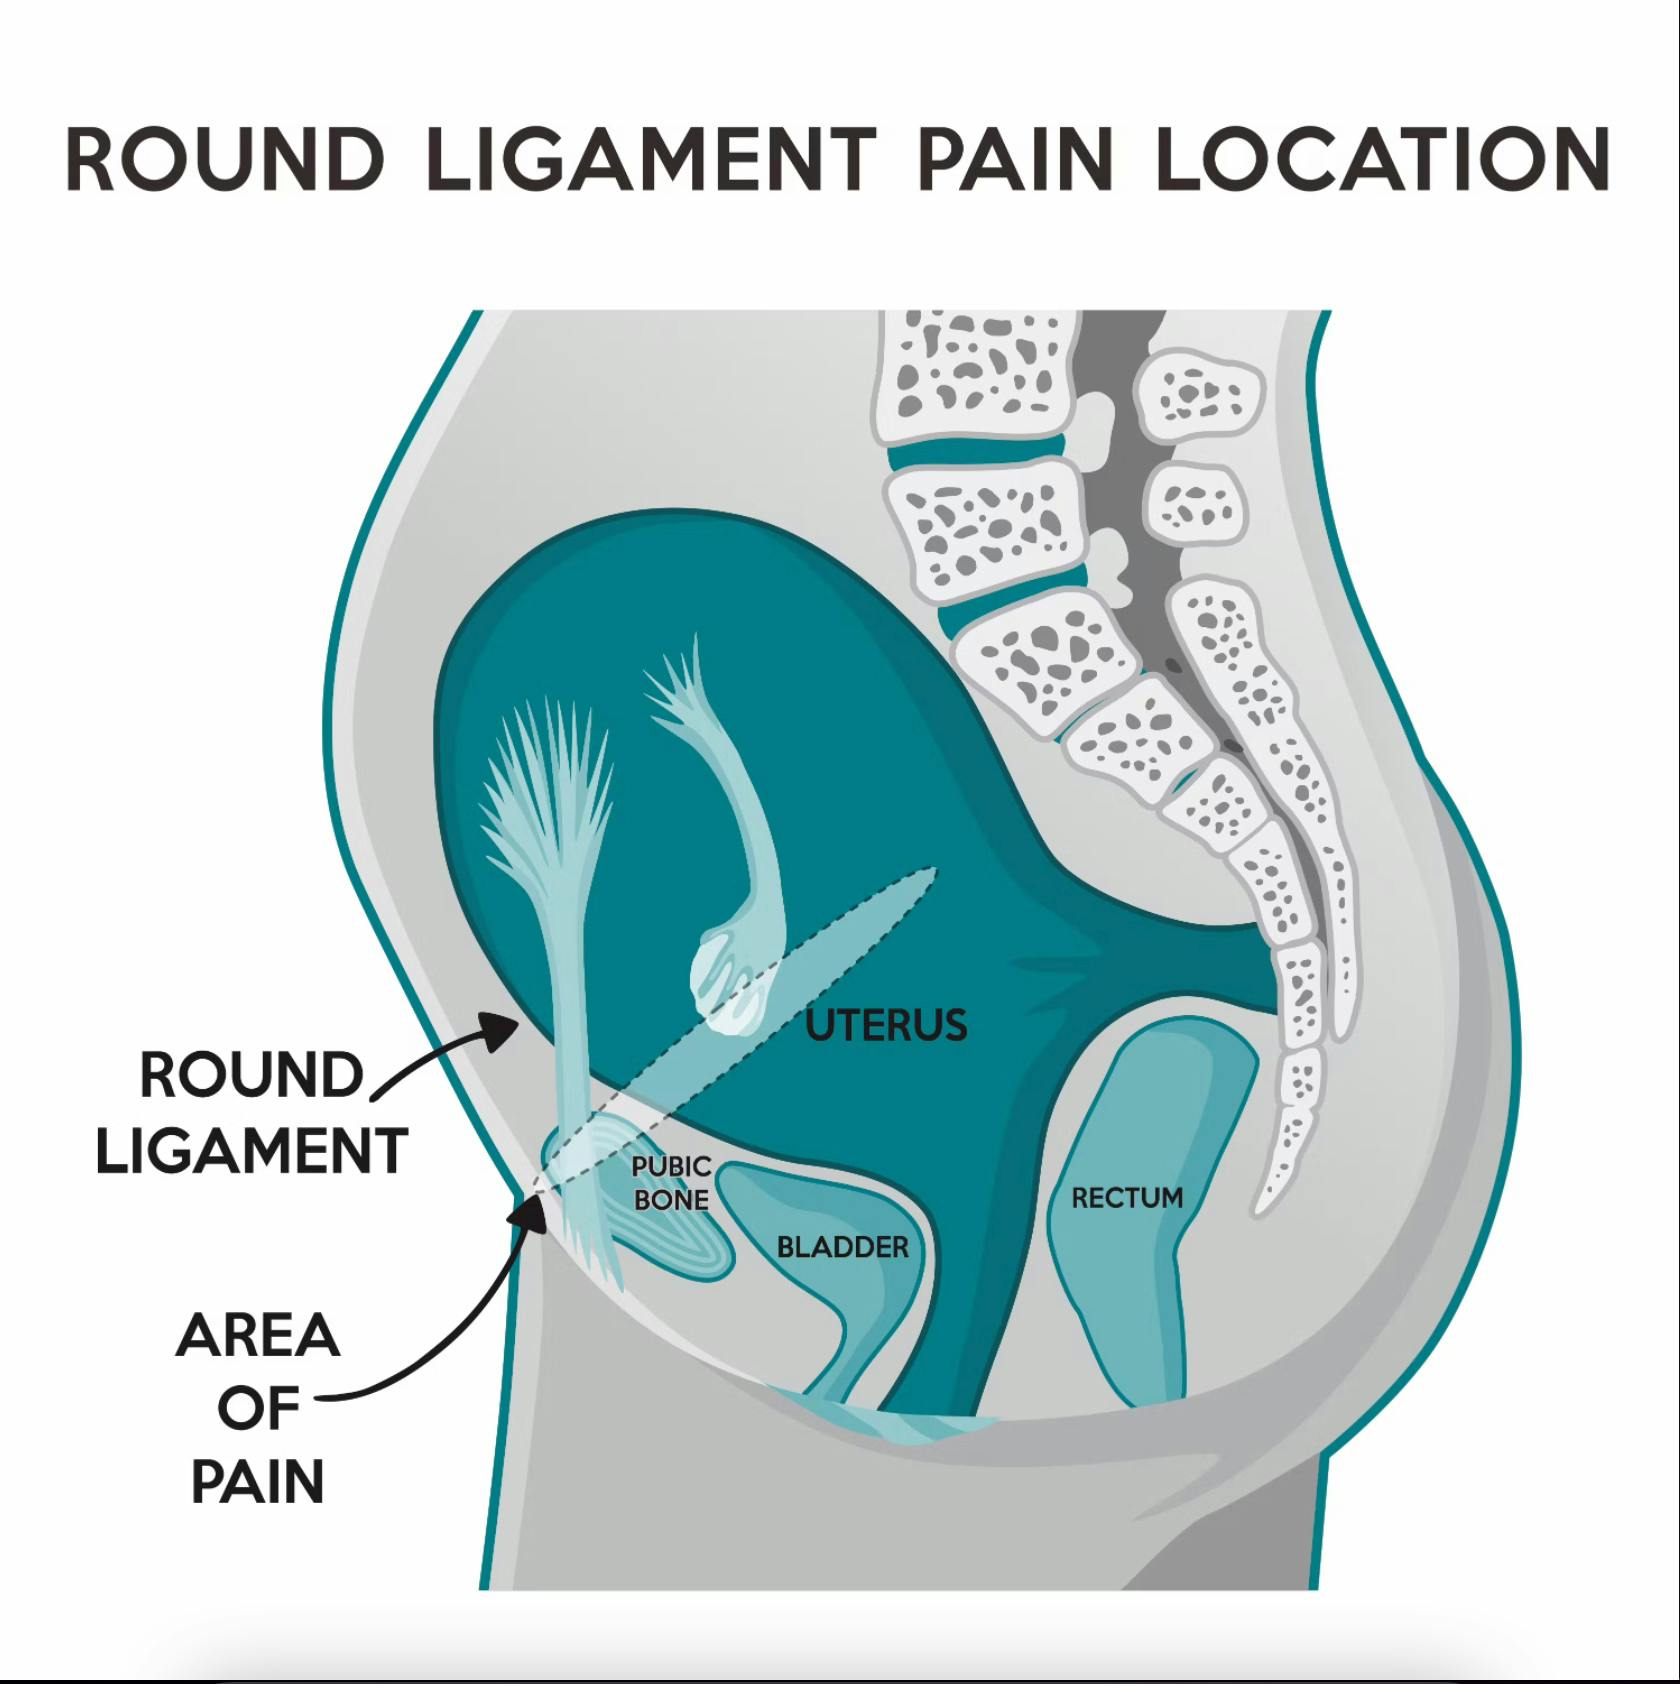

Round Ligament Pregnancy